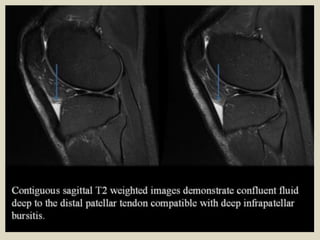

Deep Infrapatellar Bursitis

On MRI, deep infrapatellar bursitis appears as a triangular fluid collection posterior to

the patellar tendon. When found in adolescents, it should be differentiated from

Osgood–Schlatter disease. Osgood–Schlatter disease is associated with thickening and

hyperintense signal intensity of the patellar tendon, but these findings are absent in

deep infrapatellar bursitis. In addition, cases of Osgood–Schlatter disease, on clinical

examination, display pain and tenderness at the insertion of the patellar tendon.

Sagittal magnetic resonance T2 gradient showing deep infrapatellar bursal fluid.

Deep infrapatellar bursitis.